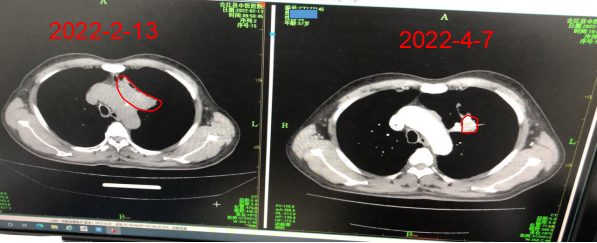

说了这么多,可能大家还会有点抽象,接下来就来看看来院患者的治疗效果图吧!

患者1:肺鳞癌,PD-L1表达90%,单药免疫治疗2个疗程后,肿瘤缩小50%以上,治疗无任何副反应。